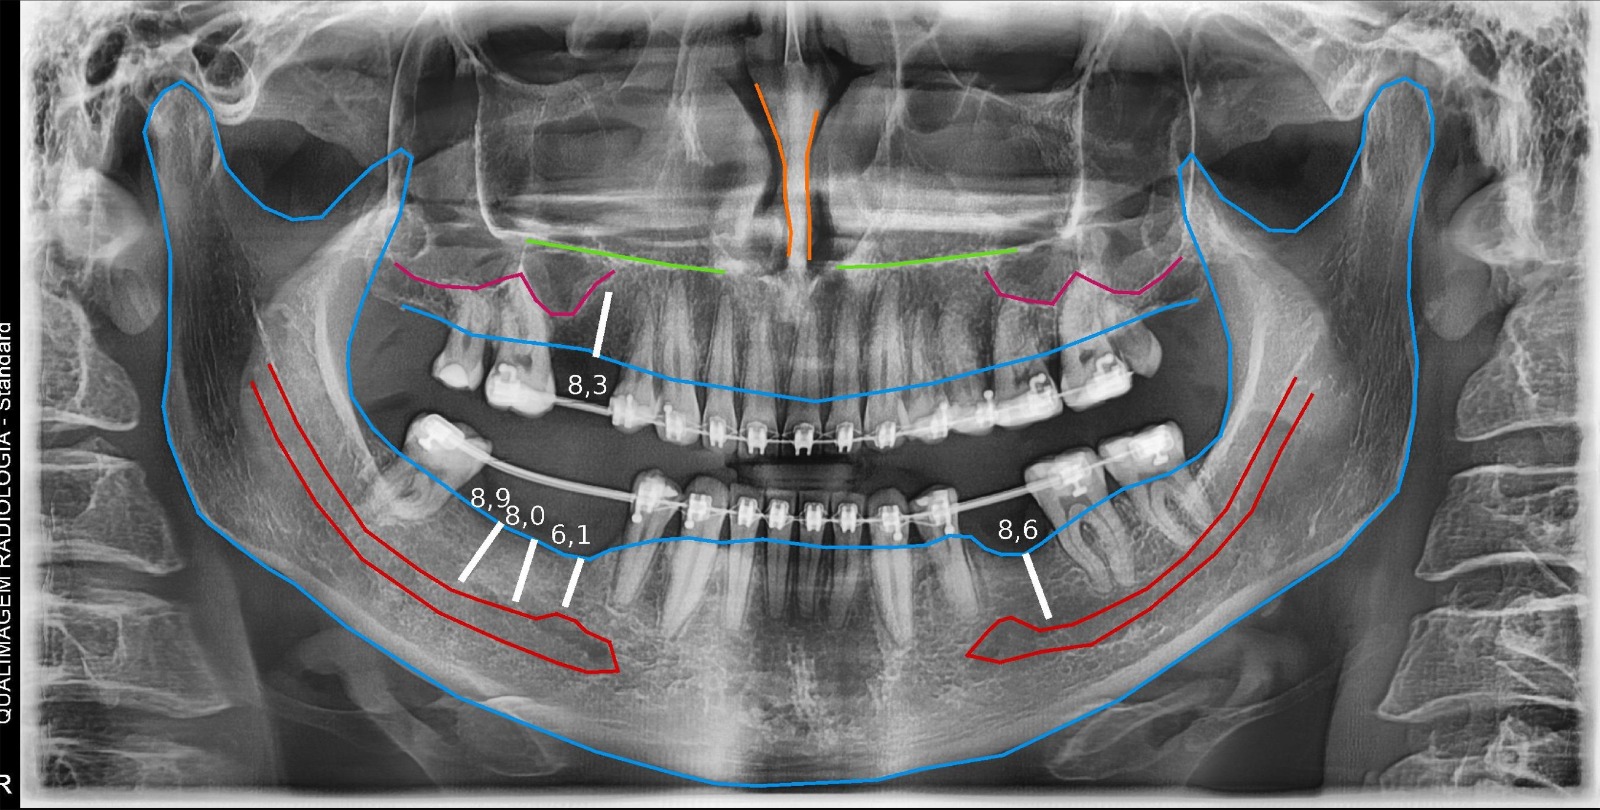

Panorâmica

Exame rápido que mostra todos os dentes e ossos da face. Ideal para diagnóstico geral.

Panorâmica para Implante

Visão ampla da estrutura óssea, essencial para o planejamento seguro de implantes dentários.